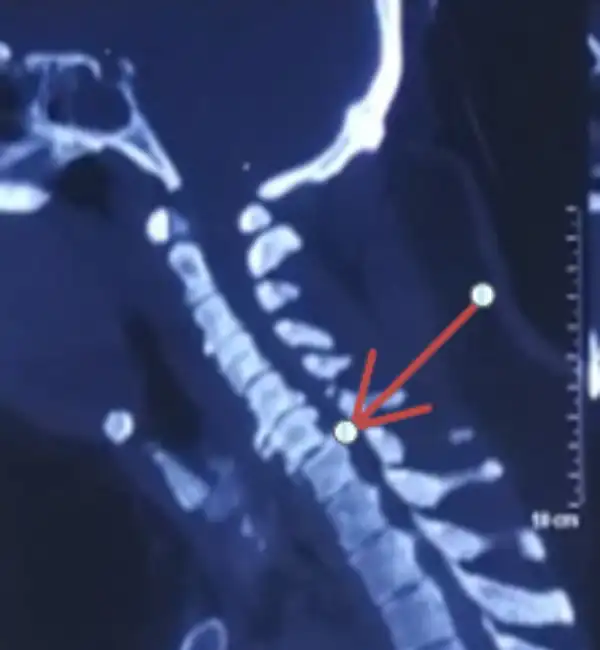

C6-7 Fracture dislocation pre op CT